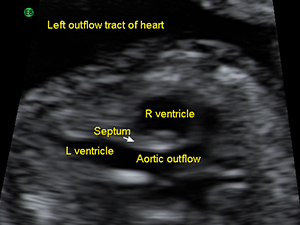

The aortic outflow tract from the fetal heart